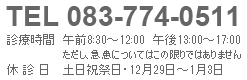

どんな部署?

血液浄化センター長の小松医師をはじめ、看護師10名、臨床工学技士3名が所属しています。透析療法技術認定士の資格を有するスタッフもおり、日々研鑽を積み専門知識や技術を磨いています。現在、約65名の患者さまが透析治療を受けておられます。

当院の血液浄化センターの良いところは?

当院には透析ベッド20床と個室ベッド1床があり、感染症が心配な場合でも個室ベッドでの透析継続が可能です。

維持透析のみならず各診療科と連携し透析ライフを支援します。また、一般病棟、地域ケア病棟、療養病棟があり、身体状態に応じて透析を継続しながら入院治療を行うことも可能です。

〇透析リハビリテーション:理学療法士・作業療法士がベッドサイドに伺い、リハビリテーションを実施。筋力低下の防止やADL(日常生活動作)の維持に力を入れています。

〇送迎バス有り:通院が困難な方のために、送迎サービスのご相談も承っております。お気軽にお問い合わせください。

〇シャントエコー:定期的なエコー検査を実施し、透析の命綱である「シャント」のトラブルを早期発見・早期治療につなげます。

〇InBody(体組成計)測定:月に一度、体組成を計測。体内の水分バランスや筋肉量を正確に把握し、最適なドライウェイト(目標体重)の設定に役立てています。

〇フットケア:フットケア指導士が定期的にフットケアを実施し、足病変の早期発見・早期治療に努めています。

〇栄養指導: 食事管理等、管理栄養士が丁寧にご相談に応じます。

透析スケジュール

当院の透析スケジュールは、月・水・金:午前と午後の2クール/火・木・土:午前と午後の2クールです。

| 月 | 火 | 水 | 木 | 金 | 土 | 日 | |

| 午前 | 〇 | 〇 | 〇 | 〇 | 〇 | 〇 | ー |

| 午後 | 〇 | 〇 | 〇 | 〇 | 〇 | 〇 | ー |

※祝日は通常どおり行っています。

目指すもの

「透析に関しては私たちにお任せを!」

ひとりひとりが責任をもって、チーム全体でタッグを組み、安心・安全な透析療法を提供していきます。

血液浄化センター長より

副院長、血液浄化センター長の小松です。安全に透析が受けられるようにがんばっています。

透析施設をご検討中の方、小さなことでも構いませんので、お気軽に当院PFMセンターにご相談ください。